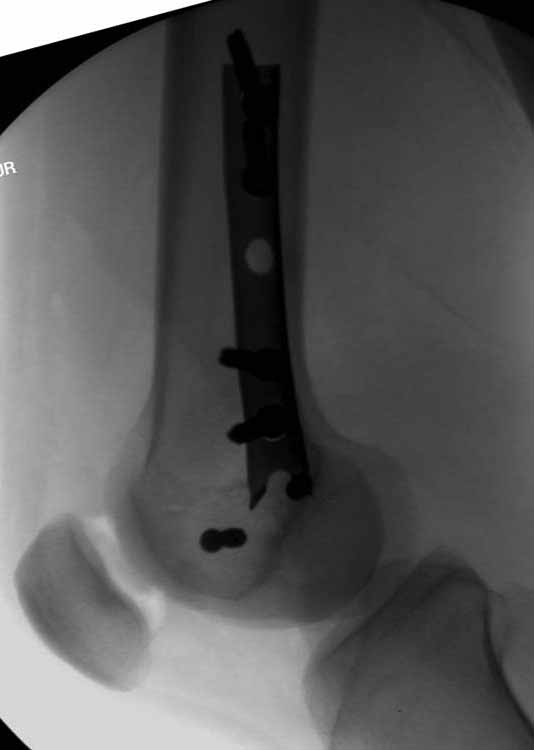

Ответ на эту часть Вашего поста – вложенный файл. Больная оперирована неделю назад по поводу открытого перелома дистального эпиметафиза бедренной кости. После операции она идёт в рентгенкабинет для выполнения послеоперационной контрольной рентгенографии, представленной на слайдах 10 и 11. Узнав, почему её фотографируют, просила передать Вам, Антон, привет.

Здесь пример медиальной пластины и латеральный комбинированный метод (у второго больного старый перелом тибиал плато, леченный где то и когда то)